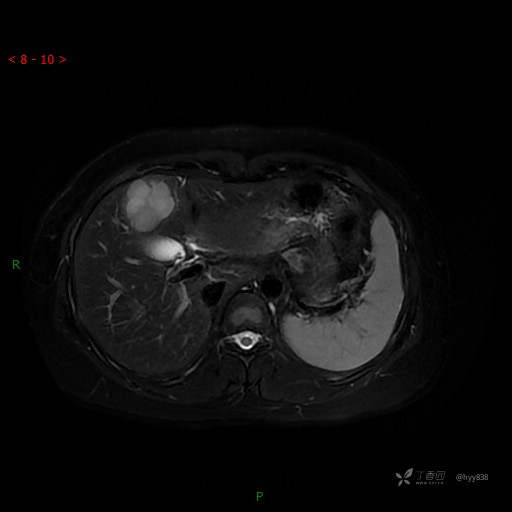

T2WI-fs